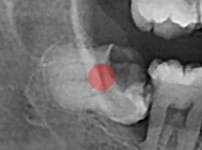

부분 매복 사랑니 발치